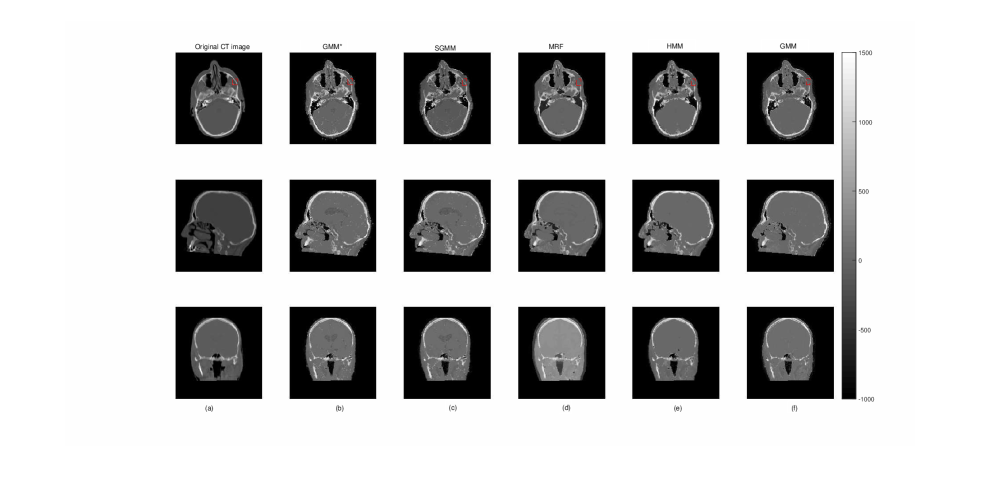

The partitioning approach had better performance in tracing bone tissues. Bone tissues appear as bright white on CT images, see Figure 5. The figure shows slices of CT image and its corresponding predicted slices for a representative patient. The first row in the figure where the images are marked by red colored box clearly shows that the partitioning approaches are better in identifying bone tissues.

Refer to caption

Figure 5: The first column (a) presents the original CT image slices and the remaining columns (b-f) show the corresponding predicted slices of CT image.

We presented the prediction errors in Figure 5, which corresponds to the predicted slices in Figure 6. It can be seen that the images of the prediction errors corresponding to the bone tissues appear darker for the partitioning approach: GMM and SGMM.